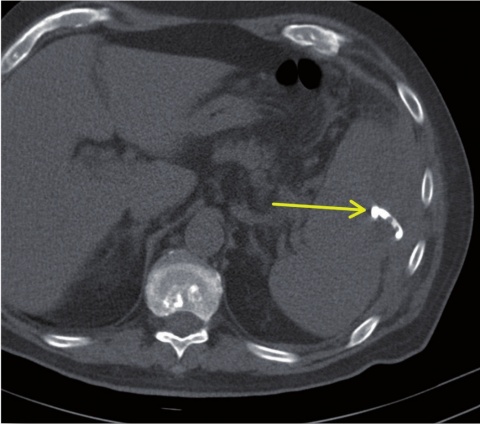

sich die regelgerecht einliegende Drainage (Pfeil). Der Abszess

konnte vollständig entleert werden.

Im interdisziplinären Konsens erfolgte noch am selben Tag die interventionelle Therapie mittels CT-gestützter Drainageneinlage. In Rückenlage wurde nach Lokalanästhesie unter sterilen Kautelen in Seldinger-Technik CT-gesteuert ein 12F-Pigtailkatheter implantiert (Abbildung 2). Hierbei entleerten sich 240 ml einer eitrig-trüben übelriechenden Flüssigkeit. Proben zur mikrobiologischen Diagnostik wurden asserviert. In der abschließenden computertomografischen Lagekontrolle zeigte sich der Milzabszess vollständig entleert und kollabiert (Abbildung 3).